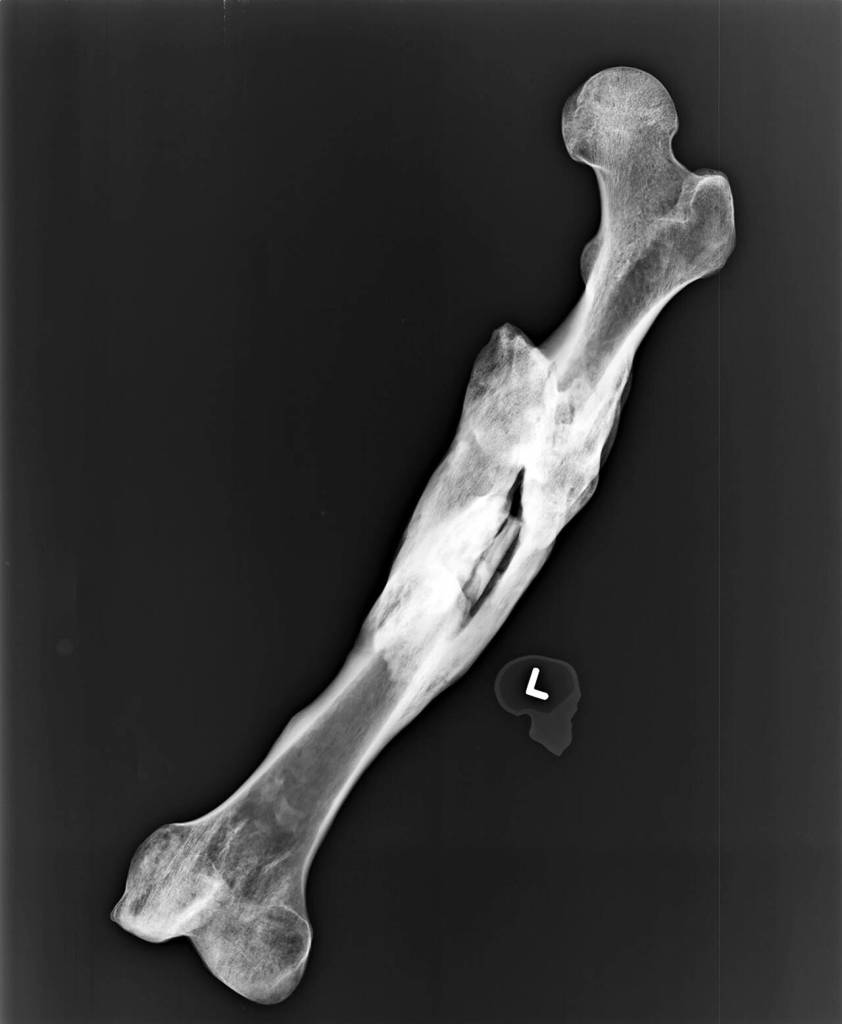

Dr. Kathy Taylor, a state forensic anthropologist, examined the exhumed bones, too. She estimated they belonged to a man with Caucasian ancestry, who stood from 5-foot-2 and and 5-foot-6. She guessed he could be anywhere from 27 to 61 years old. She saw no “perimortem trauma” — that is, trauma at or around the time of death — but she did note an unset left femur fracture that had healed awkwardly. It would’ve left him shuffling around in pain, likely for years, about 2 inches shorter on one side.

A section of the right femur was sent to the University of North Texas to extract DNA and upload it to the FBI’s database, CODIS. Those samples were obtained by March 2019. Death investigators ruled out many possible matches through DNA and dental records, but still they were without a name.

Mystifyingly, investigators couldn’t find any family members who knew anything about the badly broken leg.